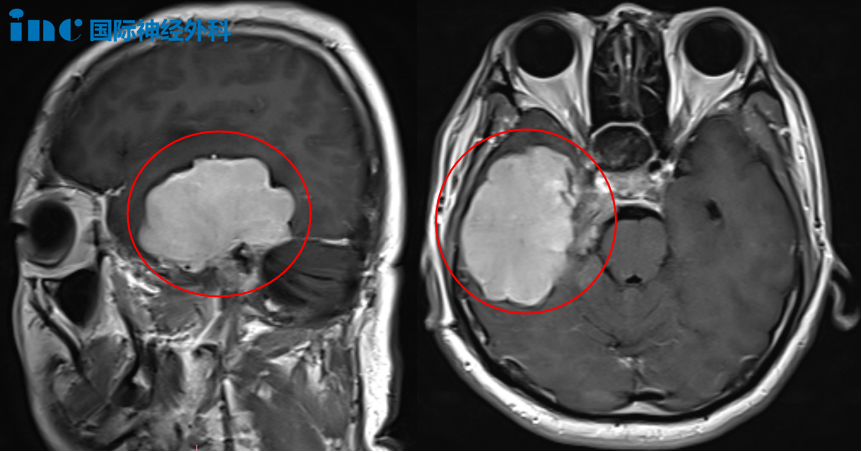

3年后,林先生复查核磁时发现肿瘤体积显著增大,右侧岩斜区、右颞底、乳突区及右侧小脑幕均被肿瘤侵犯,甚至已经把三叉神经和滑车神经360°无死角的包裹。其中右颞叶较大的病灶已达到32*31*25mm。1年多后,脑膜瘤持续生长,右颞叶较大的病灶更是达到惊人的67*49*47mm!